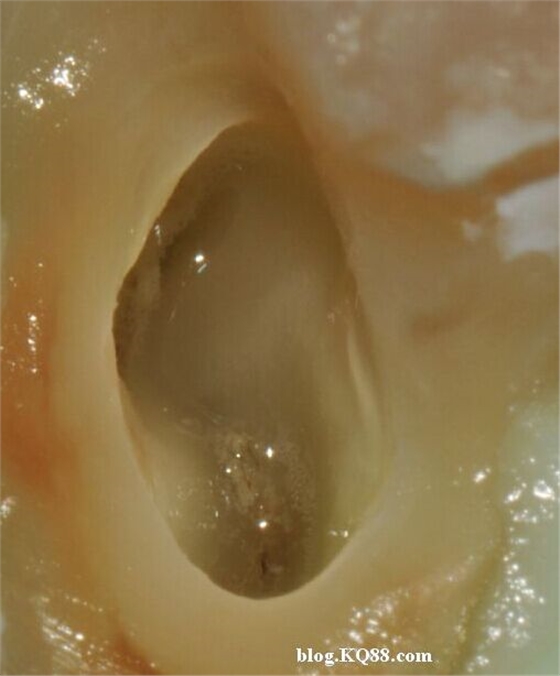

利用兩組照片說(shuō)明:A因齲拔除的智齒去腐揭髓頂后

暴露牙髓

髓腔內(nèi)放入2%左右的次氯酸鈉,通過(guò)氣泡可以看到牙髓已經(jīng)開始溶解。